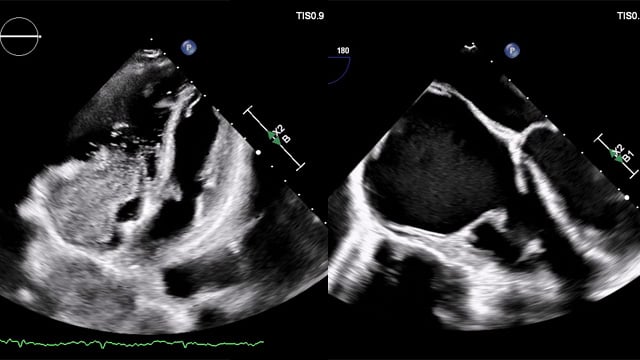

Mixed mitral valve disease in an irradiated chest with eggshell-like left atrium

A rare and complex TMVR case: 40-year-old patient, heavily calcified mitral annulus and eggshell left atrium—how would you plan and treat this challenging anatomy?